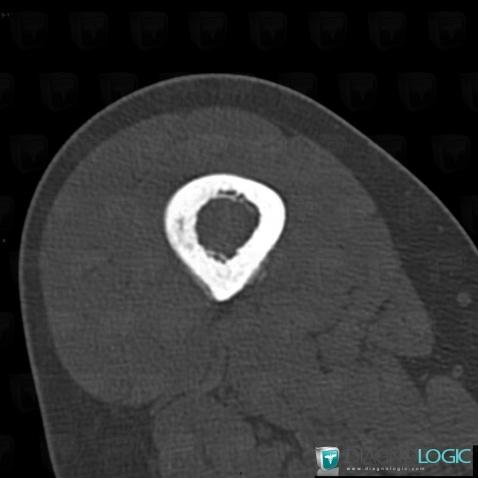

Ewing sarcoma, Femur - Mid part, CT

Here is the specific information in the key image above:

- Diagnosis Ewing sarcoma, Location(s) Femur - Mid part, with gamuts Ill-defined osteolysis, Diaphyseal osteolysis